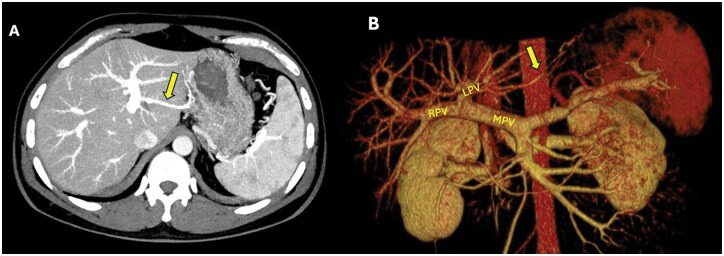

第三流是指肝脏在双重血供之外,从第三个来源增加的血供。异常的左右胃静脉、Sappey静脉和Barlow静脉以及旁静脉系统被认为是第三流最重要的例子。临床上,第三流很重要,因为它与肝脏假性脓肿有关,并在肝胆和胃手术中增加手术并发症的风险。我们的病例系列包括8例异常胃左静脉(ALGV)和1例Sappey静脉。除了介绍ALGV和供应静脉的例子外,我们还重点介绍了在肝移植供体和胃癌病例中观察到的肝脏缺血性并发症。我们的目的是强调与algv相关的手术风险和术前影像学评估血管变异的重要性。

Third inflow refers to the additional blood supply to the liver from a third source, apart from its dual blood supply. Aberrant right and left gastric veins, Sappey and Barlow veins, and the parabiliary venous system are considered the most significant examples of third inflow. Clinically, the third inflow is important due to its association with hepatic pseudolesions and its role in increasing surgical complication risks in hepatobiliary and gastric procedures. Our case series includes 8 cases of aberrant left gastric vein (ALGV) and 1 case of a Sappey vein. In addition to presenting examples of ALGV and Suppey vein, we also highlight ischemic complications of the liver observed in a liver transplant donor and a gastric cancer case. Our aim is to emphasize ALGV-related surgical risks and the importance of assessing vascular variations in preoperative imaging.